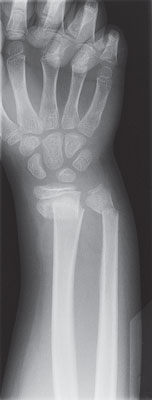

| X-ray of a broken wrist |

Find breaks or chips (fractures) in the bones.